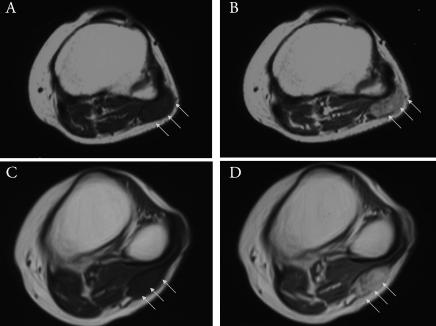

Extra-abdominal desmoid tumors preferentially affect the shoulders, arms, backs, buttocks, and thighs of young adults. Multicentric occurrence is rather rare but seems to be another distinctive feature of extra-abdominal desmoid tumors. In this article we report a rare case of multicentric extra-abdominal desmoid tumors arising in bilateral lower limbs.

腹外硬纤维瘤好发于年轻人的肩部、手臂、背部、臀部和大腿。多中心发生较为罕见,但似乎是腹外硬纤维瘤的另一个显著特征。在本文中,我们报告了一例罕见的双侧下肢多中心腹外硬纤维瘤病例。